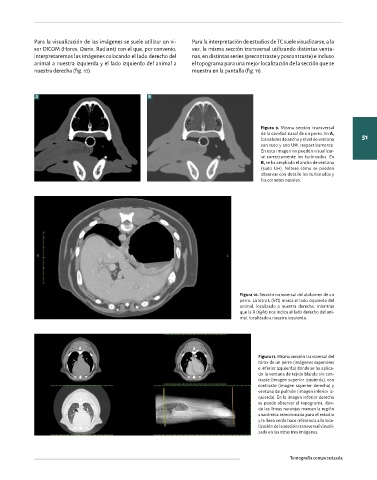

el ancho de ventana. En cambio, en la cavidad abdominal, Figura 9. Misma sección transversal

50 donde la mayoría de los órganos presentan una densidad Órgano/Tejido WW WL de la cavidad nasal de un perro. En A, 51

los valores de ancho y nivel de ventana

muy parecida (tejido blando) nos interesará un ancho de Encéfalo 100 50 son 1500 y 300 UH, respectivamente.

ventana estrecho. Hueso 1500 300 En esta imagen no pueden visualizar-

se correctamente los turbinados. En

En el caso de la cavidad nasal, si utilizamos un ancho de ven- Abdomen/mediastino 400 40 B, se ha ampliado el ancho de ventana

(3480 UH). Nótese cómo se pueden

tana estrecho no podremos visualizar correctamente los Pulmones 1500 -500 observar con detalle los turbinados y

los cornetes nasales.

Figura 11. Misma sección transversal del

tórax de un perro (imágenes superiores

Figura 8. Misma sección transversal del e inferior izquierda) donde se ha aplica-

tórax de un paciente canino. A. Los valores do la ventana de tejido blando sin con-

de ancho y nivel de ventana son 350 y 40 traste (imagen superior izquierda), con

UH, respectivamente. B. Los valores de an- contraste (imagen superior derecha) y

cho y nivel de ventana son 1400 y -500 UH, ventana de pulmón (imagen inferior iz-

respectivamente. Un ancho de ventana es- quierda). En la imagen inferior derecha

trecho permite valorar las estructuras de se puede observar el topograma, don-

tejido blando, pero no el parénquima pul- de las líneas naranjas marcan la región

monar (A), mientras que al ampliar el ancho anatómica seleccionada para el estudio

de ventana podemos valorar el parénquima y la línea verde hace referencia a la loca-

pulmonar perdiendo detalle de los tejidos lización de la sección transversal visuali-

blandos (B). zada en las otras tres imágenes.